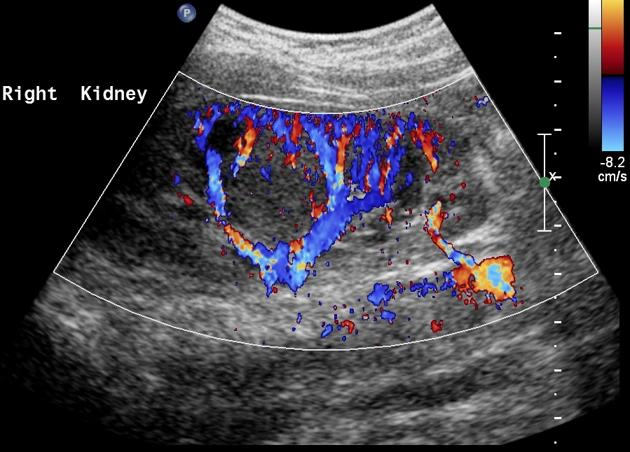

Động mạch thận phụ (Multiple renal arteries)